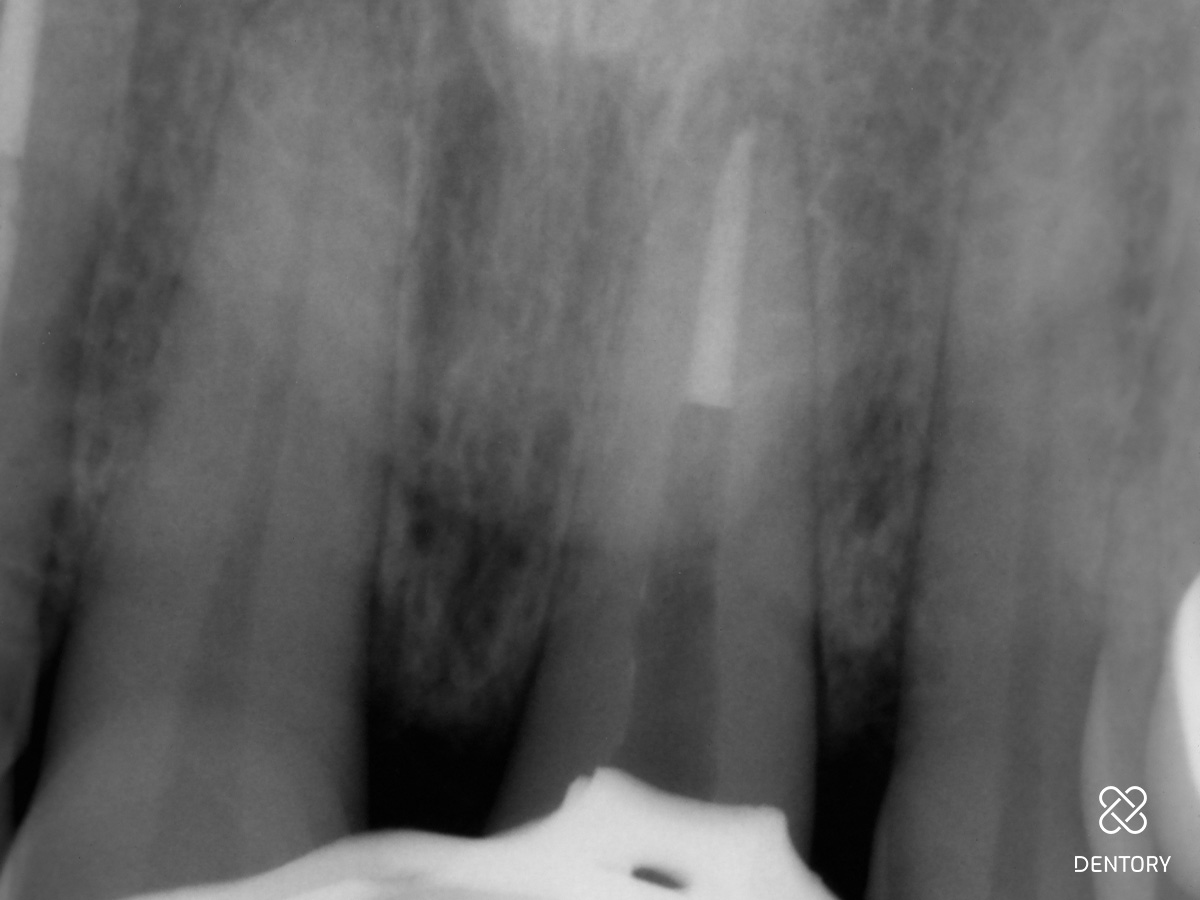

Abbildung 1

Ausgangssituation.